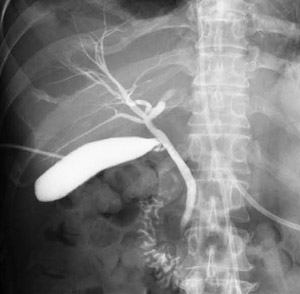

以下に,主な画像処理機能を紹介する。これらの処理は検査名ごとに細かく調整して登録でき,ユーザが検査名を選択するだけで,各検査に応じた最適な画像を提供する。例えば,消化管造影検査では透視での残像を抑え,胆嚢造影検査や肝動脈造影検査ではS/Nとコントラストを上げる処理にするなどの設定が可能である(図5)。

図5 FPD1717による胆道造影像 |

4.透視自動記録機能